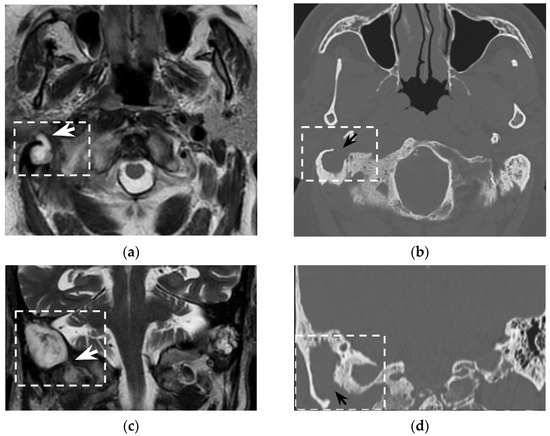

In the clinical suspicion of a Bezold’s abscess, temporal bone CT and contrast enhanced neck CT are the gold standard [7] for defining two main diagnostic aspects: (1) the site of mastoid bone erosion in the context of a mastoiditis and (2) the anatomical boundaries of the neck suppurative collection. Temporal bone CT typically shows signs of mastoiditis, such as opacification of the mastoid cells and erosion of the mastoid bone trabeculae. High resolution (slice thickness < 1 mm), coronal plane reconstructions, high frequency bone kernel and bone window are suggested to enable the detection of small bone interruptions at the mastoid tip, generally at the digastric groove (Figure 4).

However, despite its crucial pathogenic role for the suppurative path, bone defects in the mastoid tip have been precisely outlined only in around half of all literature reports (51/97 patients, 53%). Indeed, in 7/97 patients (7%) the mastoid tip was considered intact, revealing that the diagnosis of Bezold’s abscess can be achieved even without overt bone erosion, especially in younger children (3/7 patients were younger than 5 years old). The incomplete pneumatization of mastoid cells before the age of five is well known and is supposed to hinder the diffusion of the suppurative process across the thickened mastoid bone wall. Before the age of five, more destructive infectious processes or emissary vein bone canals likely allow Bezold’s abscess occurrence [8]. A recent case of a woman affected by Goldenhar syndrome with an unremarkable mastoid bone (Figure 5) highlighted those atypical origins of Bezold’s abscess that should be accurately investigated in syndromic patients [15].

Figure 4. Eighty-seven-year-old man with history of external mycotic otitis. T2w MRI in axial (a) and coronal (c) planes show abnormal right mastoid (dotted rectangle) filled with hyperintense material that spreads into the neck (white arrows). Axial (b) and coronal (d) bone CT images show opacified right mastoid, absence of bone trabeculae, and a wide defect (black arrows) at the mastoid tip. Images were consistent with an infected cholesteatoma eroding the mastoid tip and spreading into the neck. The finding was confirmed at surgery.

Tomography 08 00074 g004